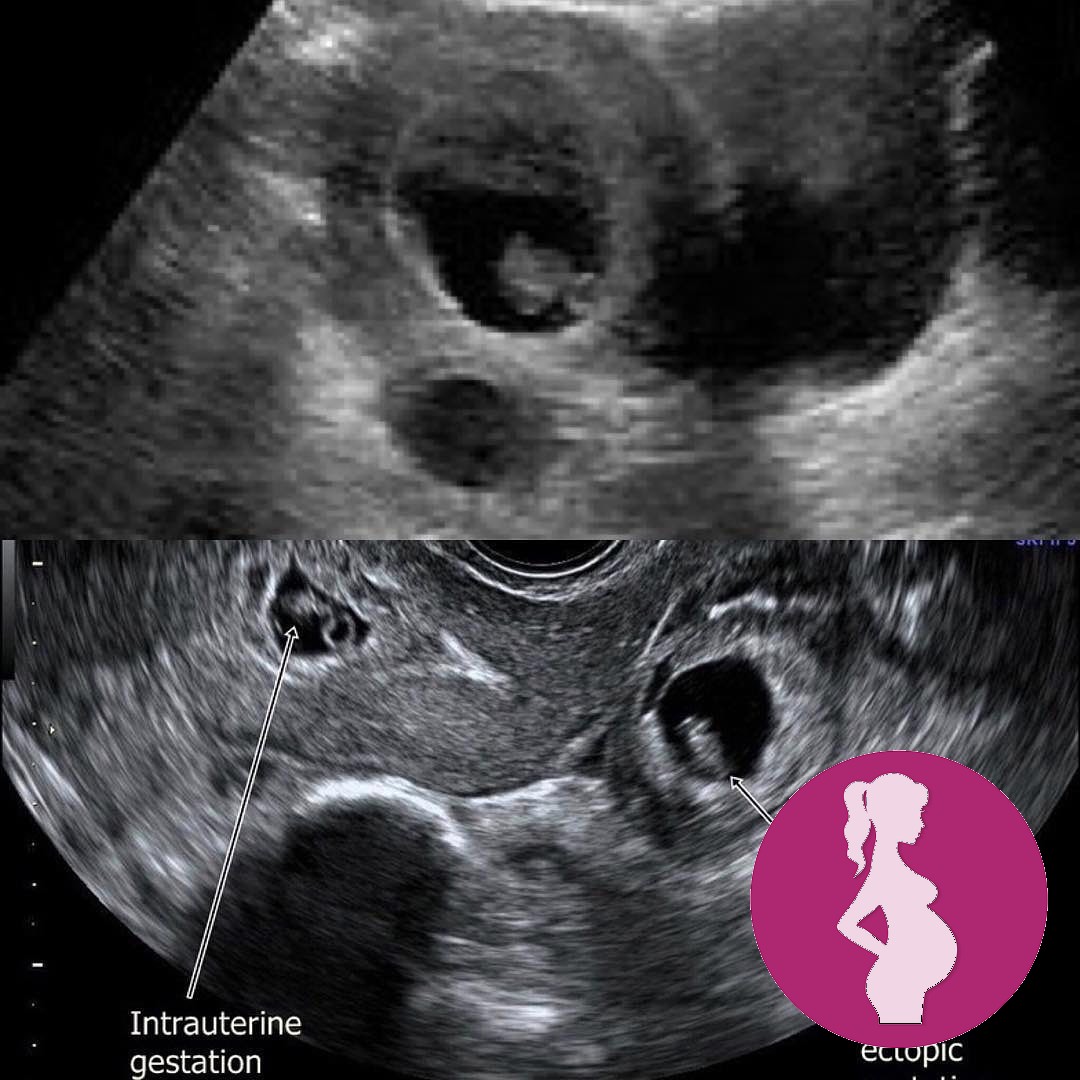

This is why a TRANSVAGINAL ultrasound scan is so important in the early weeks of pregnancy.

The top image is a transabdominal scan showing an intrauterine pregnancy and a possible ovarian cyst.

The bottom scan is a transvaginal scan showing the intrauterine pregnancy and a co-existing ectopic pregnancy.

Although still rare, heterotropic pregnancies are on the increase due to the number of women having assisted conception.

It is so important for a scan to be performed by a qualified sonographer who has in depth knowledge and experience of early pregnancy complications

We thank God for the early diagnosis and removal of the ectopic pregnancy and the ongoing intrauterine pregnancy 🙏🙏🙏